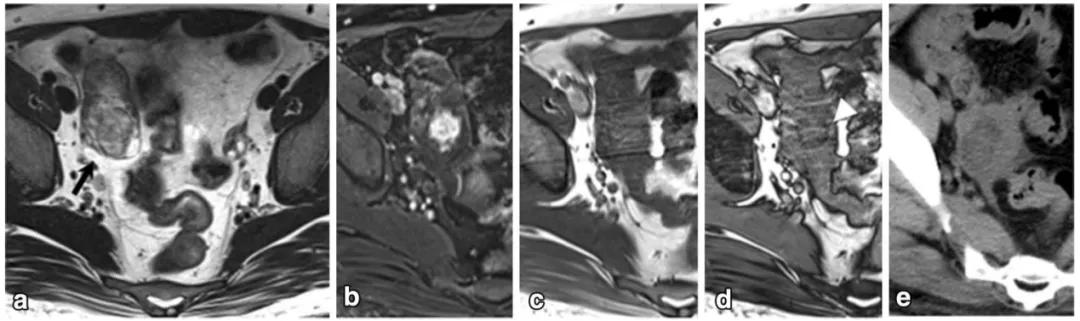

女,65 岁,左侧卵巢纤维瘤。图 a 箭头显示肿物 T2WI 呈低信号,DWI 未见明显扩散受限(b),增强扫描缓慢强化(c 增强早期,d 增强晚期)

女,70 岁,卵泡膜细胞瘤。图 a 增强扫描显示右侧卵巢肿物(白箭),同时子宫内膜增厚(图 a 白箭头及图 b 黑箭)。

女,32 岁,富于细胞性纤维瘤。右卵巢实性为主肿物,T2WI 稍高信号(图 a),DWI 高信号(图 b),增强扫描渐进行强化(c 增强早期,d 增强晚期)